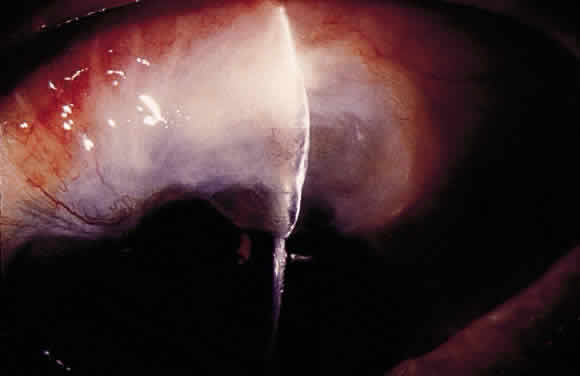

The initial management of early postoperative hypotony with a formed anterior chamber is conservative. Topical steroids and cycloplegics are used. Restrictions in activity (bending, weight lifting) and avoidance of Valsalva-positive conditions are recommended, especially in patients at risk for suprachoroidal hemorrhage (see earlier). If there is hyposecretion related to intraocular inflammation, ciliochoroidal detachment, or both, the initial treatment consists of intense corticosteroid therapy and long-acting cycloplegics, which stabilize the blood-aqueous barrier. Intervention is indicated in patients with hypotony associated with other complications and in persistent, low IOP with loss of visual acuity and hypotony maculopathy. After filtration surgery, prompt management is indicated, also when there is loss of bleb height. Treatment should be aimed at correcting the specific cause of hypotony. When there is lens-corneal touch (flat anterior chamber, grade III) immediate surgical intervention is necessary to prevent endothelial damage and cataract formation (see Chapter 15). Reformation of the anterior chamber with air, balanced salt solution, or, preferably, a viscoelastic can be done at the slit lamp or under the operating microscope through the paracentesis made intraoperatively. Viscoelastic material is best for maintaining, at least temporarily, the anterior chamber depth. When there are large and appositional choroidal effusions, drainage of the fluid also is necessary (Fig. 4). The technique is described in detail in Chapter 15.

When hypotony results from overfiltration of a filtering bleb, several options are available. A large bandage contact lens,15 symblepharon ring,16 and Simmons' shell17 can be helpful. Bandage contact lenses should have a diameter of at least 16 to 17 mm to cover the filtering bleb. They are not efficient in severe and chronic cases. The Simmons' shell is a 22-mm, dome-shaped rigid shell of transparent polymethylmethacrylate. A raised platform on the concave inner surface of the shell is positioned over the sclerostomy site. The curvature is designed to selectively indent the perilimbal area when pressure dressing is applied. The Simmons' shell usually is effective; however, it may be uncomfortable. Tonometry is not possible to monitor the IOP. Decentration of the shell is frequent unless sutured to the conjunctiva. It requires close (daily) monitoring, and corneal complications (epithelial defects and abrasions) are common. It is particularly difficult for monocular patients. Several chemical and thermal treatments have been used to induce an inflammatory reaction in the filtering bleb, which modify the morphologic features of the filtering blebs and increase the IOP. These procedures include topical application of 0.25% to 1% silver nitrate or 50% trichloracetic acid to the bleb surface,18 cryotherapy,19 diathermy and cauterization,20 argon laser,21 and, recently, the neodymium:yttriumaluminum-garnet (Nd:YAG) thermal laser.22 More than one treatment session might be needed to achieve the desired goal. Possible complications include postoperative discomfort, bleb leak, transient increase in IOP, and corneal edema. Cryotherapy is best done under retrobulbar or peribulbar anesthesia. The probe is applied initially to the lateral borders of the bleb. Before starting the freeze, firm pressure is applied with the cryoprobe to bring the bleb surface tissues into apposition with the underlying sclera. Several applications (two to five) using a temperature of -50° to -80°C and a duration of application of 10 to 30 seconds are used. Nd:YAG thermal laser treatment of overfiltering and leaking blebs has been described more recently. It is best done under regional anesthesia. For this procedure, the continuous-wave mode is required. Energy levels range between 3.0 and 4.0 J, with the laser offset between 0.9 and 1.2 mm and the aiming beam focused in the conjunctival epithelium. The goal is to induce whitening and wrinkling of the conjunctival epithelium. A grid pattern of 30 to 40 spots of laser is placed over the entire bleb. Postoperatively, oral aqueous suppressants and a compressive or “torpedo” (i.e., cotton plug placed directly over the bleb surface) patch are used during the first 48 hours. Injection of autologous blood into the bleb can reduce overfiltration and resolve bleb leaks.23–26 Inflammatory cells and serum proteins from the injected blood may accelerate the inflammatory and healing process, which decreases filtration (Fig. 5). Possible complications include hyphema, endophthalmitis, increase in IOP requiring surgical intervention, bleb failure, corneal blood staining, and corneal graft rejection.27–30 Finally, surgical revision may be needed.31–35 Resuturing the scleral flap and scleral patch grafting (when resuturing is not possible) have been successfully used in patients with hypotony maculopathy associated with overfiltering the filtering bleb. Alternatively, two sets of stitches in the scleral flap, with one set tied tightly, can raise the IOP, stretch the sclera, and flatten chorioretinal folds. Sliding conjunctival flaps or free conjunctival grafts also can be helpful (see later).